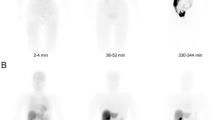

Biodistribution and dosimetry comparison across six different PET radiotracers

Representative PET images of each radiotracer biodistributions are displayed in Fig. 1 (iterative reconstruction method) and Supplementary Figure 2 (FBP reconstruction method with correspondent time-activity curves shown in Supplementary Figure 3).The highest [18F]FDG uptake was observed, as expected, in the brain, heart, kidneys and urinary bladder. For the peptide-based radiotracers, the highest uptake was observed in the kidneys and appeared from highest to lowest in [18F]ENC2015 and [18F]ENC2018, then [18F]AlF-NOTA-NOC and [18F]AlF-NOTA-OC and finally [18F]AlF-NOTA-RGDfK.